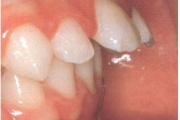

Normaalse jäävhammaskonna pilt küljelt ja eest vaadatuna.